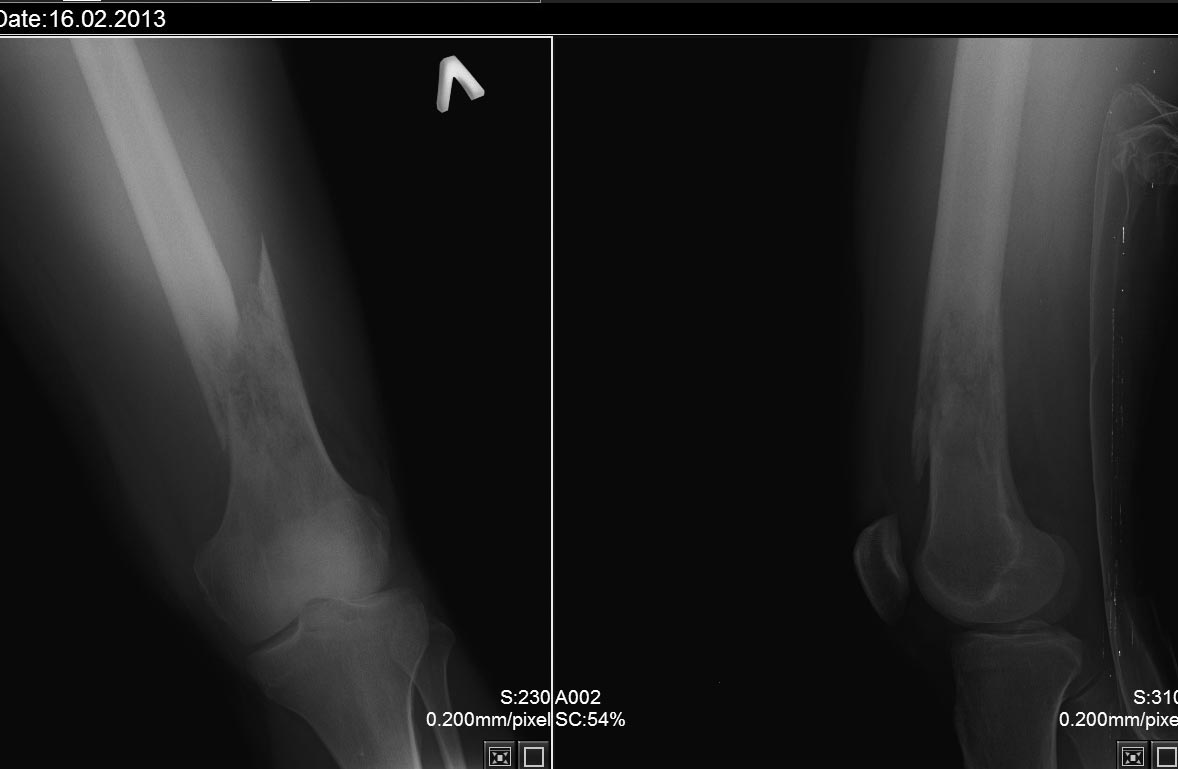

[Ortho] остеогенная саркома бедра?

Уважаемые коллеги! Прошу высказать свое мнение и порекомендовать тактику.

16.02.13поступил молодой человек 26 лет с переломом бедра.Травма при

падении на улице.

Ранее отмечал боли в коленном суставе поврежденной , лечился у

ревматолога с синовитом. В настоящее время проводится ДСВ. Хотелось бы

узнать мнения о диагнозе и где лучше оперировать такого пациента.